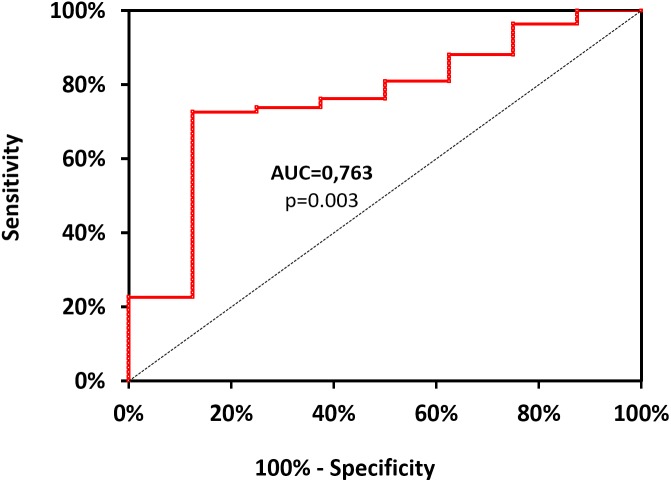

With the use of ROC curve analysis (Figure 2) on data including divers (n = 92), Ctrl+ being asymptomatic and therefore used as negative event, the threshold value of mtDNA, predictive of clinical symptoms was determined as >16726.106 copy of mtDNA/μL, with corresponding values of sensitivity and specificity as follows: 73% (95% CI, 62–81%), 87% (95% CI, 50–99%). Positive-predictive and value negative-predictive value are 98 and 23%, respectively. OR and LR values are as follows: OR = 18.56 (95% CI, 3.01–114.16); likelihood ratio: LR+ = 5.810 (95% CI, 0.925–36.510) and LR- = 0.313 (95% CI, 0.202–0.484). Area under the curve, explaining differences in the frequencies between symptomatic or asymptomatic, is 0.763 (95% CI, 0.589–0.938) and its significantly different from 0.5 (Fisher test: p = 0.003). This test failed to distinguish sick divers from healthy non-divers when including all subjects (n = 114, p > 0.05).

FIGURE 2.

Receiver operating characteristic curve for mtDNA values. It is designed from data including lonely divers (n = 92), Ctrl+ being asymptomatic and therefore used as negative event. Positive events include Medullary Vestibular and Cerebro-Medullary DCS. The threshold value of mtDNA, highly predictive of clinical symptoms was determined as >16726.106 copy of mtDNA/μL, with corresponding values of sensitivity and specificity as follows: 73% (95% CI, 62–81%), 87% (95% CI, 50–99%). Area under the curve (AUC), explaining differences in the frequencies between symptomatic or asymptomatic, is 0.763 (95% CI, 0.589–0.938) and its significantly different from the dotted line (p = 0.003).